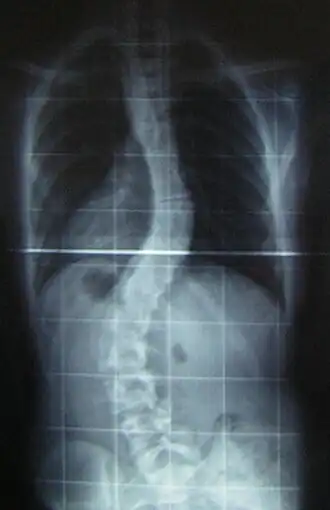

Radiologie

Les clichés nécessaires sont une radiographie du rachis dorso-lombaire de face et de profil, fait chez un patient debout, avec compensation préalable d'une asymétrie de longueur des membres inférieurs[2].

Le principal critère d'évaluation de la scoliose est l'« angle de Cobb », qui se mesure sur une radiographie du rachis de face. C'est l'angle formé à partir de l'intersection de deux droites tangentielles l'une au plateau supérieur de la vertèbre limite supérieure, l'autre au plateau inférieur de la vertèbre limite inférieure. Les conventions médicales veulent qu'un angle inférieur à 10 degrés ne soit pas considéré comme une scoliose à part entière[35]. On peut classer les courbures scoliotiques en fonction de leur importance :